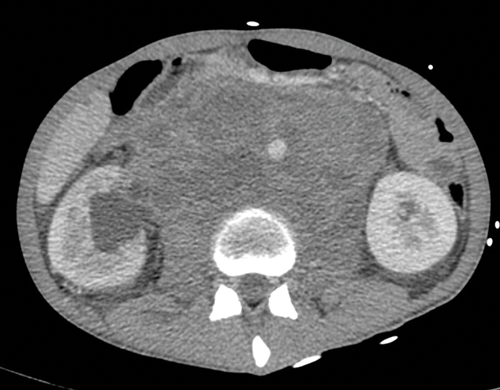

Stage two disease has abdominal lymph nodes; 2a nodes <2cm, 2b nodes 2-5cm, 2c at least one node >5cm. Retroperitoneal lymph nodes are the commonest site for metastatic disease and left sided tumours tend to spread to left para-aortic lymph nodes (Figure 3) and right sided tumours to aorto-caval or precaval nodes [3] (Figure 4). It is important to carefully evaluate the relevant area depending on the site of the tumour.

Figure 5. Massive retroperitoneal lymphadenopathy causing effacement of

the IVC, anterior displacement of the aorta and right hydronephrosis.

Figure 6. Coronal CT showing left para-aortic lymph node in the same patient as Figure 3.

Nodes may be massive and encase renal vessels, displacing the aorta or inferior vena cava (IVC) and this is important when reporting the staging CT (Figure 5). Coronal views can be very useful to demonstrate the overall length of nodal disease as sometimes, on axial imaging the size of the nodes can be underestimated (Figure 6). Teratoma nodes may contain some areas of calcification or low attenuation areas of necrosis, which are less often seen in seminoma lymph nodes. Retroperitoneal lymph nodes often respond very well to chemotherapy agents, but teratoma nodes may require retroperitoneal lymph node dissection if they do not respond or there remains a sizable node at the end of the treatment.